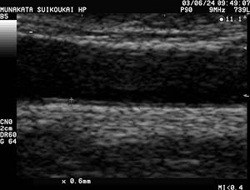

頚動脈エコー例

頚動脈エコー

正常例

動脈の拡大エコー

(黒く帯状に抜けているところが頚動脈の内腔)